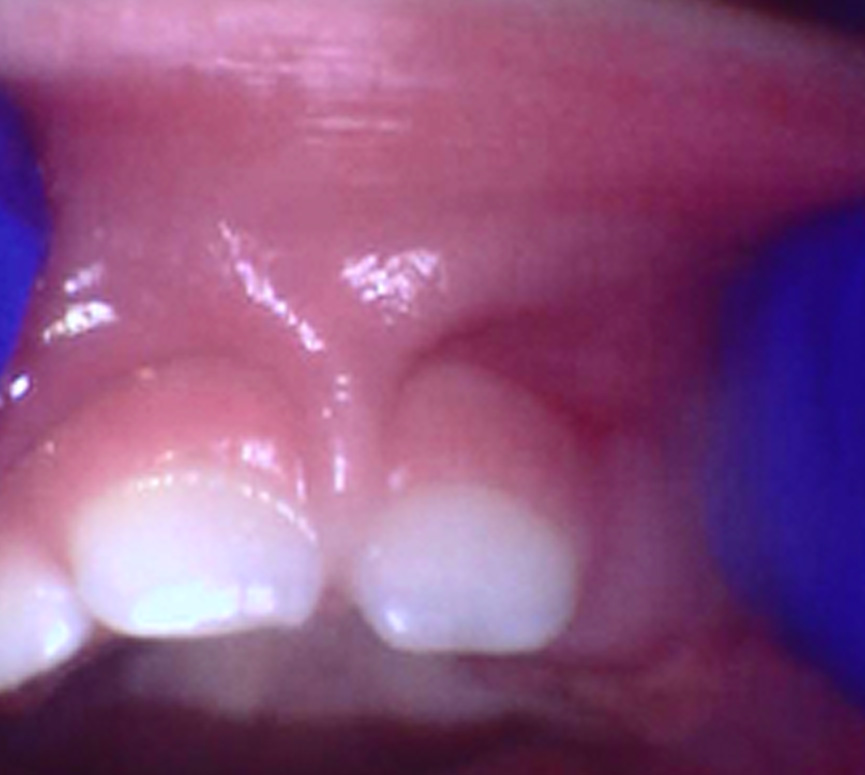

Frenectomy: Before and After

How a Frenectomy Helps

A frenectomy is a simple procedure that releases the restrictive frenum, allowing for natural movement of the lip or tongue. At our practice, we use a LightScalpel carbon dioxide laser—a modern, minimally invasive tool designed for precision and comfort.

CO₂ laser technology minimizes inflammation and promotes quicker recovery. Most children experience immediate improvement in movement.

Following release, many infants show better latch and feeding, while older children benefit from enhanced speech, swallowing, and tongue mobility.